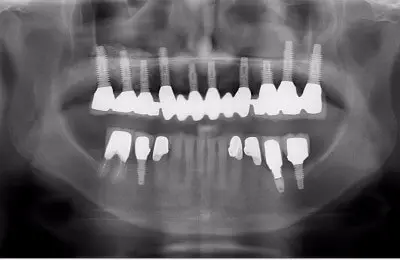

Sinus Bone Regeneration With Implants - Case Study